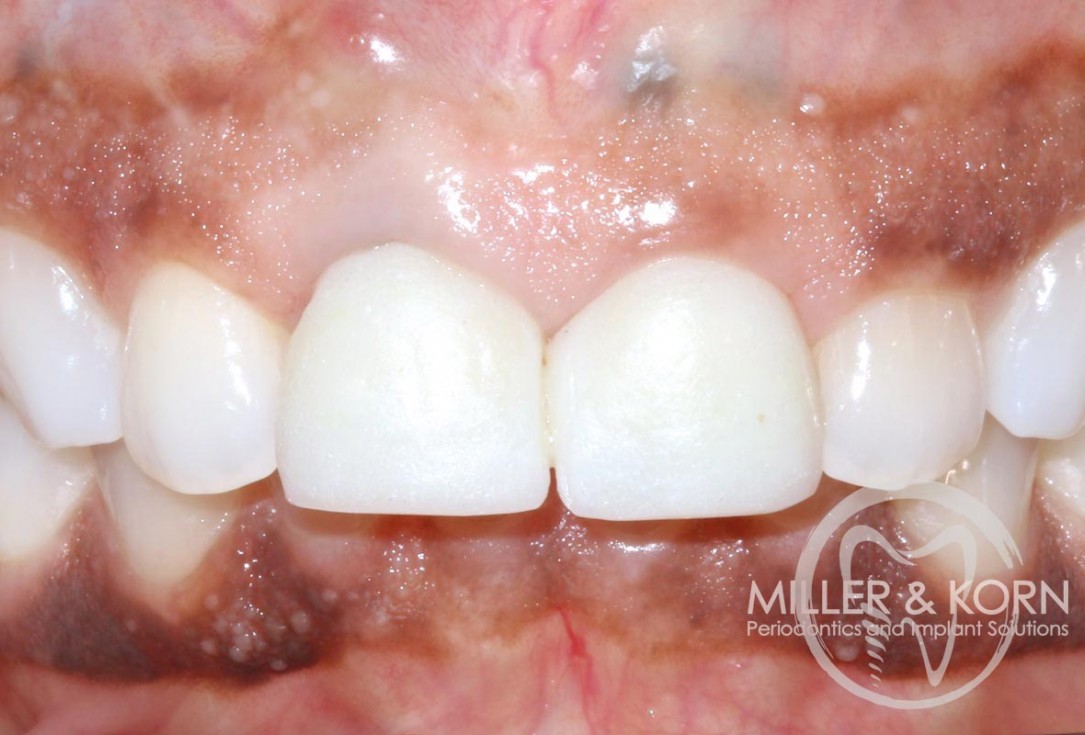

1/22 - 60-year-old female patient presented with a chronic infection on tooth #11. Since she has a high lip line matching the gingival margins of the adjacent central incisor and creating a root eminence is extremely important. For these reasons, the treatment of choice was an allograft bone ring enabling immediate placement of the dental implant with simultaneous regeneration of her ridge.Immediate implant placement and regeneration of ridge using an allograft bone ring and Jason® membrane - Drs. Miller and Korn

2/22 - She experienced trauma as a child and had fractured both tooth #8 and 9 which had been crown several times for esthetics.Immediate implant placement and regeneration of ridge using an allograft bone ring and Jason® membrane - Drs. Miller and Korn

60-year-old female patient presented with a chronic infection on tooth #11.

Since she has a high lip line matching the gingival margins of the adjacent central incisor and creating a root eminence is extremely important. For these reasons, the treatment of choice was an allograft bone ring enabling immediate placement of the dental implant with simultaneous regeneration of her ridge.